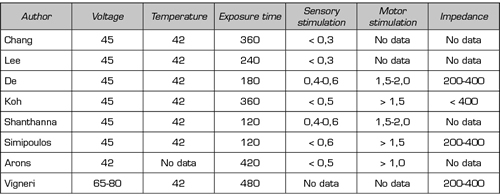

In the present literature search, eight prospective randomized studies (23,26-32) and nine quasi-experimental studies (33-41), of before-and-after type, were found evaluating the efficacy of PRF of the DRG. It should be noted that, in the former, there is high clinical heterogeneity in relation to the control group used as a comparator, and to other interventions used before and after the evaluated procedure (e.g., steroids or local epidural anesthetics) (Table I). This heterogenicity makes difficult to interpret results and prevents the proper conduct of a meta-analysis (3). Table II shows the parameters used in the application of pulsed radiofrequency in the eight randomized prospective studies.

Table II. Parameters used in the treatment of pulsed radiofrequency of the dorsal root ganglion in the eight randomized studies analyzed

There are still many questions to be answered about the different aspects of basic knowledge of this technique, which can have a significant impact on the results obtained from its clinical application. As an example, aspects such as treatment location, timing, and optimal PRF parameters remain to be determined. As for the first point, it remains to be established whether the application of PRF on a single DRG is sufficient to achieve a satisfactory beneficial result or whether, on the other side, given the divergent distribution of nociceptive afferents along several adjacent metameres, PRF needs to be applied to several dorsal root ganglia of neighboring segments. With regard to timing, it would seem clear that the modulating effects described to date are temporary, remaining to establish until now the value of repeating the procedures, taking into account that the pathophysiological alterations of chronic radicular pain are maintained over time. Finally, it is interesting to explore whether modifying PRF parameters (such as voltage, frequency, and duration of treatment), selected so far empirically, can have an impact on better results. While it would seem reasonable to maintain the electrode tip at 42 degrees Celsius, as it is the basis for safety in the use of the technique, exposure time and voltage could be the parameters to be modified. Exposure time is the most frequently modified factor (2,3). Most studies use one or more 120-second cycles, as this is considered safe, in terms of tissue injury. Thus, there are studies using 180, 240, 360 and 480 seconds of total duration (2,3). A randomized, double-blind clinical study of patients with unilateral radicular lumbar pain is currently ongoing in our department, comparing the analgesic efficacy of PRF for 240 and 480 seconds, administered in two pulses.

Other authors, such as Vigneri, suggest to increase the voltage between 65 and 80 volts to increase the efficiency of the technique while preserving the safety profile of the PRF (22,23).